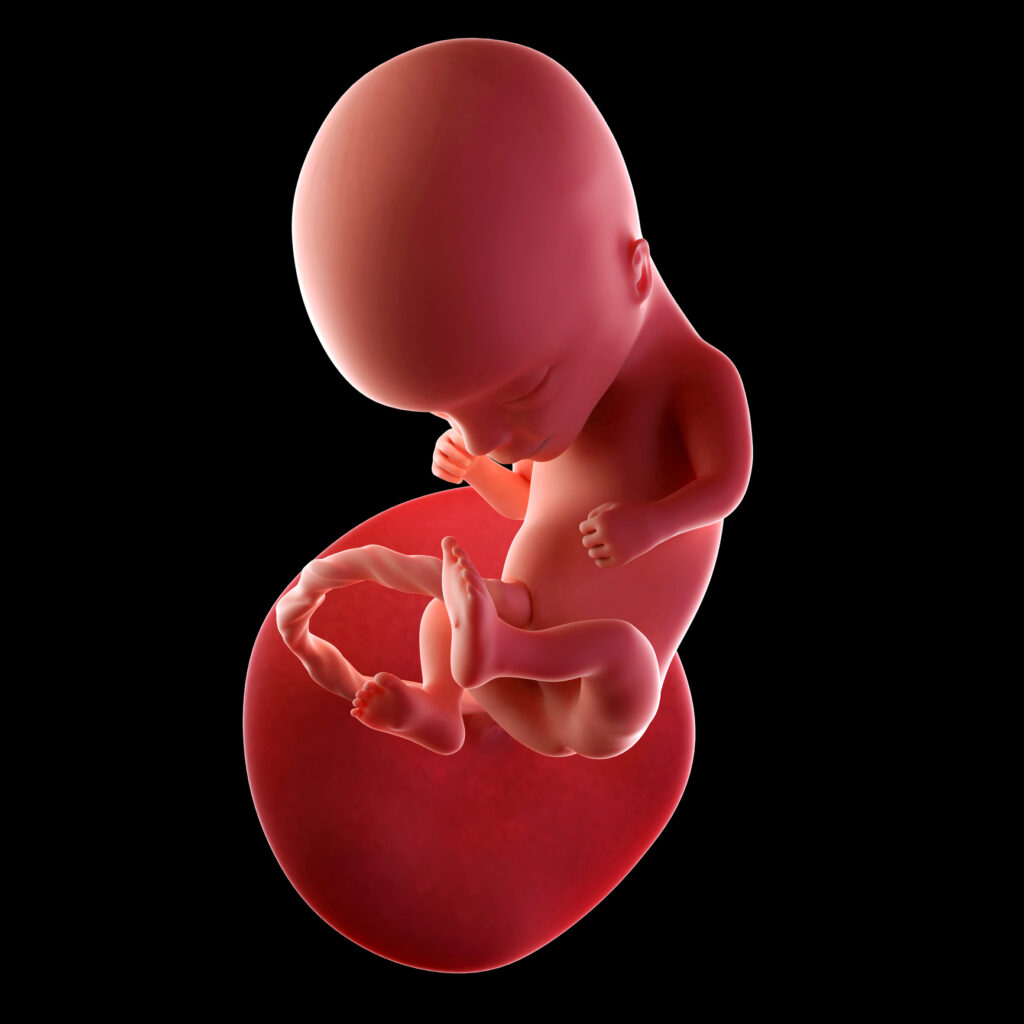

Twoje dziecko ma teraz około 8-9 cm długości (CRL) i waży około 25-40 gramów – wielkością przypomina kiwi lub małą mandarynkę.

Proporcje ciała stopniowo się wyrównują – głowa nadal jest duża, ale szyja wydłuża się, pozwalając na swobodniejsze ruchy główki.

Twarz jest coraz bardziej ludzka – oczy są bliżej siebie, uszy mają już ostateczne miejsce po bokach głowy.

Powieki są wciąż zamknięte, ale dobrze chronią rozwijające się oczy.

Dziecko potrafi poruszać ustami, robić mimiczne grymasy i ćwiczyć odruch ssania – wkładając kciuk do ust.

Kończyny są coraz bardziej smukłe i zwinne – dziecko zgina stawy, porusza palcami, a na ich końcach widać drobne paznokcie.

Skóra jest jeszcze cienka i przejrzysta, ale zaczyna pokrywać się delikatnym meszkiem – lanugo – który pomoże utrzymać maź płodową na skórze.

Serce bije około 150-160 razy na minutę, pompując krew przez całą sieć rozwijających się naczyń.

Mózg rozwija się dynamicznie – powstają kolejne połączenia nerwowe, które pozwalają na coraz bardziej skoordynowane ruchy.